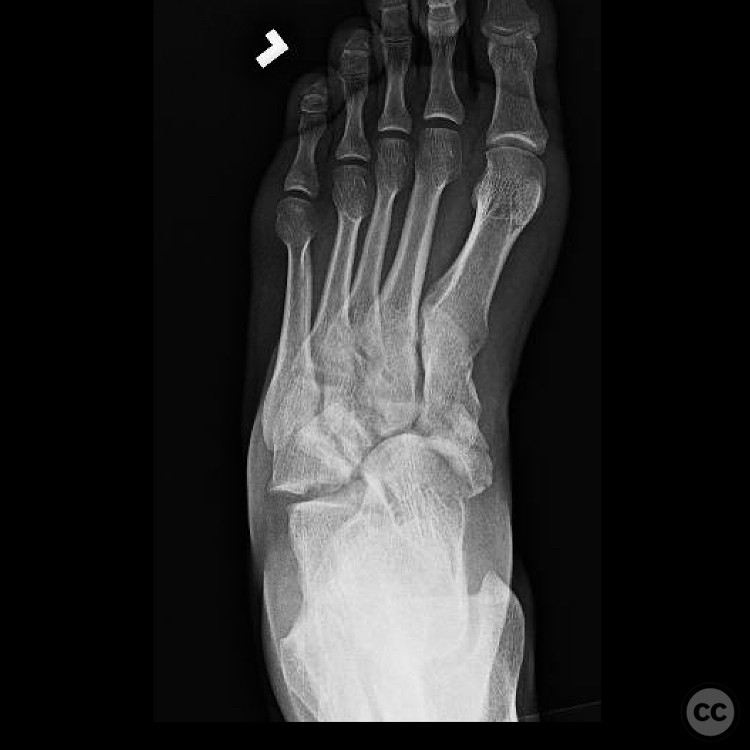

Navicular - AO/OTA 83x

Jul 27 2025

By orthopaedic_trauma

Highly Comminuted Navicular Fracture Dis...

Seattle, United States

Foot - AO/OTA 8x